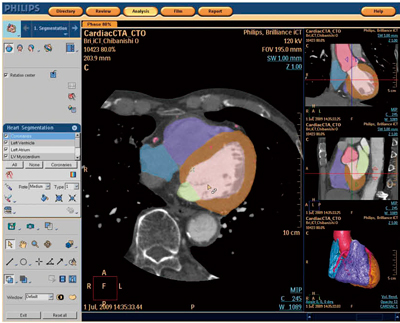

心臓CT撮影は,いまやルーチン検査の1つとなり,多くの施設で施行されている。心臓CT検査は,撮影さえすれば終了とはならず,必ず解析を行わなくてはいけない。したがって総合的に見ると,心臓CT検査は多くの時間を必要とされる。そのため,C.C.A.では“ゼロクリック”での解析を可能とした。これは,撮影後のデータ転送,アプリケーションの起動,心臓区域分け,冠動脈の抽出,左心耳削除までも全自動で行う最新機能であり,作業時間を短縮することができる(図4)。また,C.C.A.のファンクションステージでは,左右の房室容量の測定,心機能解析が可能となっている。

図4 Comprehensive Cardiac Analysis(C.C.A.)